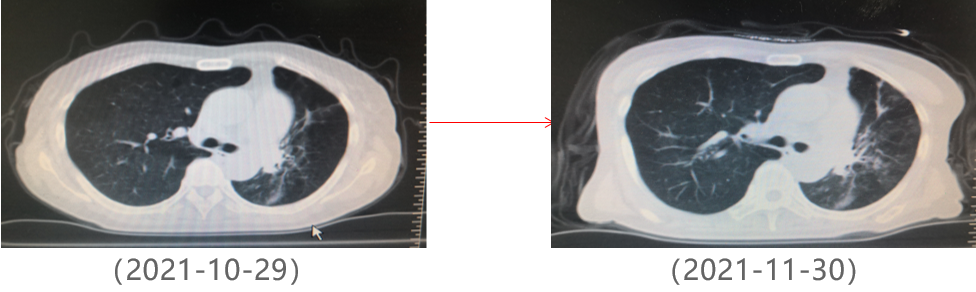

为提升肺癌前线免疫联合抗血管治疗的诊疗观念,学习与追踪肺癌领域诊疗最前沿知识,充分交流免疫/抗血管用药不良反应管理临床经验,【An例说】肺癌病例项目,征集大量临床高质量免疫联合抗血管治疗肺癌病例,并邀请全国各区域中青年及高职称医生与顶级TOP KOL互动发声!通过理念结合实践,研究结合病例,线上联动,共同促进学术由KOL/ROL向中青年医生下沉,为提升我国肺癌诊疗整体水平势在必行。免疫治疗的出现,特别是以PD-1/PD-L1为代表的免疫检查点治疗的出现,对于转移性的晚期肺癌患者而言,给患者增加了更多治疗的选择,同时,多项临床研究表明免疫治疗显著延长了患者的生存期及生活质量。为此,河北北方学院附属第一医院为您带来一例“双安疗法”用于二线治疗小细胞肺癌病例的治疗分享。 案例详情 基本情况 患者,霍xx,女,60岁。 初治时间:2020-10-16 既往史:COPD 4年,间断口服茶碱治疗,否认其他慢性病史及传染病史。否认过敏史。 个人史:无特殊 家族史:无特殊 ADL评分:90分;Khorana评分1分 入院初步检查结果 体格检查: COPD 4年,间断口服茶碱治疗,否认其他慢性病史及传染病史。否认过敏史。 个人史、婚育史、家族史无特殊。 辅助检查 血常规、肝肾功、凝血功能无明显异常。 肿瘤标志物(特异性+异常指标)。 肿瘤标志物变化趋势 NSE(神经元特异性烯醇化酶)变化趋势: NSE变化趋势 基线情况: 2020-10-16,患者无明显诱因出现咳嗽、咳痰,偶有痰中带血,伴胸闷气短4个月于我院就诊:查胸部CT:胸廓左侧塌陷,左肺上叶尖后段及下叶支气管截断,左肺下叶见软组织密度团块。右肺中叶容积小。左主支气管内见高密度影,纵隔多发肿大的淋巴结,胸膜厚,左侧少量胸膜腔积液。 浅表淋巴超声、全身骨扫描等检查提示肺外脏器未见异常。 肺部CT提示左肺占位伴阻塞性肺炎、纵隔淋巴结肿大,左侧胸腔积液。 患者遂就诊于解放军81集团军医院行支气管镜检查提示小细胞肺癌。 影像学检查 诊断结果 1.左肺小细胞肺癌(广泛期)伴胸膜转移、伴纵隔淋巴结转移 2.阻塞性肺炎 3.慢性阻塞性肺疾病 诊疗依据 (CSCO)小细胞肺癌诊疗指南2020 05治疗经过 第一阶段治疗: 胸部CT对比:较前片(2020-10-16)对比:左肺上叶复张且高密度影明显吸收;左肺占位及纵隔淋巴变化不明显,左侧胸腔积液基本吸收。 胸部CT检查对比 胸部CT对比:较前片(2020-11-26)对比:左肺占位变化不明显;纵隔部分淋巴结增大。 胸部CT检查对比 胸部CT对比:较前片(2020-12-30)对比,左肺占位明显增大,隔巴结增大,左侧胸腔新发积液,左肺上叶膨胀不全,左肺上叶新发片状高密度影。 胸部CT检查对比 胸部CT对比:较前片(2021-03-02),左肺占位性病变较前增大,纵膈肿木淋巴结较前增大。 胸部CT检查对比 胸部CT对比:较前片(2021-04-04)左肺中心型肺Ca伴左肺不张,较前增大。右肺中叶不张。纵隔多发肿大融合淋巴结,部分包绕上腔静脉,较前增大。心包少量积液、主肺动脉干增粗。左侧胸腔积液(±)。 胸部CT检查对比 头颅CT对比:2021-06-21头颅CT:考虑左枕叶、右颞叶转移瘤。尾状叶头密度增高。 头颅CT检查对比 腹部CT:较前片(2021-04-04)左肾上腺增粗,考虑转移瘤? 腹部CT检查对比 第二阶段治疗:免疫+安罗替尼。ADL评分:70分;Khorana评分3分。 胸部CT对比:对比前片(2021-06-21),左肺占位减小,纵隔部分淋巴结减小,胸腔积液吸收。 胸部CT检查对比 头颅CT对比:对比前片(2021-06-21):颅内占位变化不著。 头颅CT检查对比 胸部CT对比:对比前片(2021-07-27):左肺占位减小,纵隔部分淋巴结减小;左肺上叶片状高密度影略显吸收。 胸部CT检查对比 胸部CT对比:对比前片(2021-8-23):左肺占位及纵隔淋巴结有所减小。 胸部CT检查对比 胸部CT对比:对比前片(2021-10-29):左肺占位及纵隔淋巴结变化不著。 胸部CT检查对比 头颅CT对比:较前片(2021-07-01)对比:左枕叶、右颞叶占位明显减小。 头颅CT检查对比 胸部CT对比:对比前片(2021-11-30):左肺占位及纵隔淋巴结变化不著,腹部较前变化不著。 胸部CT检查对比 目前情况:患者神清,精神尚可,无咳嗽咳痰,偶有喘憋气短,饮食睡眠尚可,二便正常。 面部及双手皮疹样改变。 目前诊断: 1. 左肺小细胞肺癌(广泛期)伴胸膜转移、伴纵隔淋巴结转移、伴脑转移、伴肾上腺转移 2. 慢性阻塞性肺疾病 3. 下肢静脉血栓形成 4. 低钠血症 ADL评分:80分;Khorana评分2分 06病程回顾 专家点评 该病例,女性,无吸烟史,既往自2014年开始反复因咳嗽、咳痰、咯血于我院门诊或住院治疗,诊断为右中叶、双下肺基底段支气管扩张伴感染。2020年10月再次因咳嗽、咳痰、咯血行肺CT检查,检查结果示:支气管扩张、左下肺占位。后经支气管镜检查左下肺癌,病理为小细胞癌。结合肺CT:纵隔淋巴结肿大,左侧胸腔积液;临床诊断为:原发性支气管肺癌(左下广泛期小细胞肺癌)。PS评分1分,依据2020年CSCO小细胞肺癌指南Ⅰ级推荐选择化疗+免疫治疗,化疗方案:CE/EP,IC/IP,免疫治疗:atezolizumab。本病例中,患者因经济条件所限,未使用atezolizumab,化疗采用CE\EP\ZP一线及二线LE(共计7疗程),肺部病灶增大,左肺完全不张,脑转移,肾上腺转移,PS评分3分。再次依据CSCO指南,行颅脑放疗,采用PD-1(卡瑞丽珠单抗)+EP+安罗替尼(口服小分子多靶点抗血管生成药物)2个疗程后,肺部病灶明显缩小,颅内病灶消失,评效为PR;后因卡瑞丽珠单抗副作用:反应性皮肤毛细血管增生症(RCCEP)及手部皮肤皲裂,改换为派安普利单抗+EP+安罗替尼治疗,直至目前。左肺完全复张,病情明显改善,PS评分降至2分。 该患者全程治疗过程分析,单纯化疗疗效不显著,PD-1联合抗血管生成靶向药物后,使得患者病情控制,生存带来了希望。“双安”治疗方案副作用小,对PS评分高的患者也适用。派安普利单抗是唯一采用IgG1亚型且经FC段改造的新型PD-1单抗,副作用较国产其他IgG4亚型 PD-I更小;安罗替尼为口服小分子多靶点络氨酸酶抑制剂,靶点更加全面,疗效更优。采用“双安”治疗广泛期小细胞肺癌,本例虽为个例,但为临床医生提供了可践行的治疗方向,也期待着更多临床研究数据的公布,为小细胞肺癌的治疗提供强有力的治疗依据。 病例分享 王布 教授 河北北方学院附属第一医院呼吸科副主任医师,医学硕士 河北省中西医结合睡眠专业会委员 张家口市抗癌协会肺癌专业委员会委员 世界中医药学会联合会整合肿瘤专业委员会委员 在《Translational Cancer Research》、《Journal of biological regulators &homeostaticagents》、《中国临床药理学》、《中华结核与呼吸杂志》等杂志上发表学术论文10余篇,其中《川芎嗪联合顺铂影响Lewis肺癌小鼠移植瘤生长及微血管生成的研究》论文在2015年中国药学大会暨第十五届中国药师周上报告交流 荣获河北省科技进步三等奖1项,河北省医学会科技奖一等奖1项 目前以第一主研人主持河北省科技厅课题1项,市厅级课题2项 以第二主研人主持张家口市财政厅支持课题1项;河北省政府资助专科能力建设和专科带头人培养课题1项 获“河北省抗击新冠肺炎先进个人”、“河北省优秀共产党员”、“河北省冀青之星”、张家口市“最美科技工作者”,“张家口市抗击新冠肺炎先进个人”、“张家口市优秀共产党员”等荣誉称号。 专家点评 支学军 教授 河北北方附属第一医院主任医师 教授,河北北方学院硕士研究生导师 任河北省医学会内科学分会委员 张家口市医学会呼吸分会常务委员兼秘书 张家口市抗癌协会理事会理事 张家口市抗癌协会肿瘤临床化疗专业委员会常务委员 张家口市抗癌协会抗癌药物专业委员会常务委员等职务 从事呼吸科工作30余年,擅长肺部感染性疾病、肺癌、肺结核等疾病的诊治。